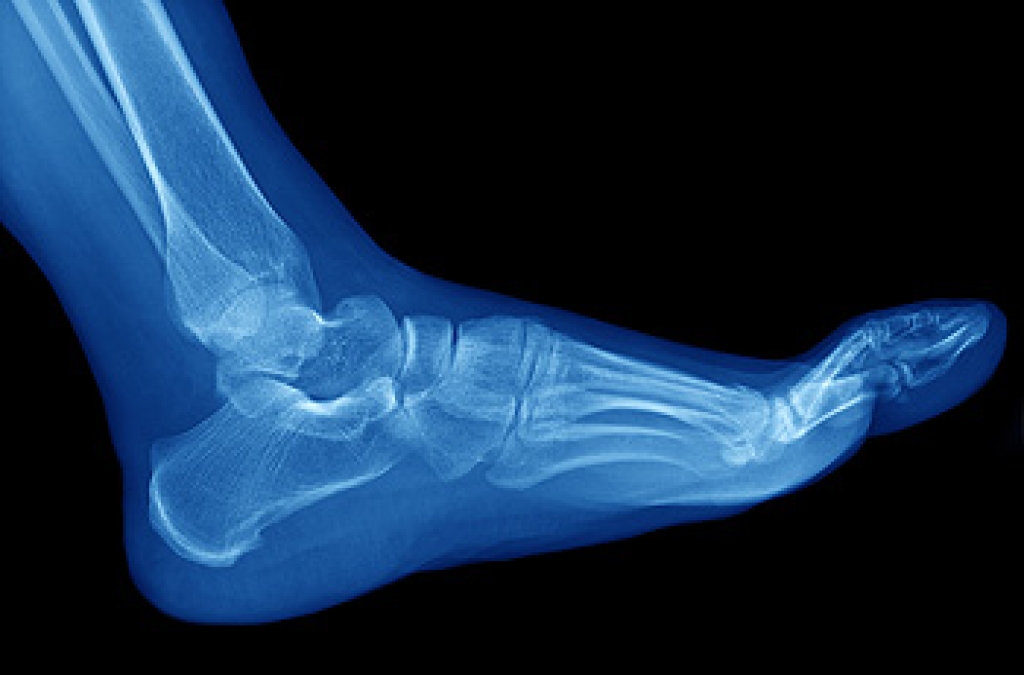

Our feet and ankles are marvels of engineering, combining intricate structures to support our weight and facilitate movement. The remarkable anatomy of the foot consists of 26 bones, comprising the tarsal, metatarsal, and phalangeal bones, forming arches that provide stability and flexibility. Ligaments connect these bones, acting like tough rubber bands to hold the structure together. Meanwhile, muscles and tendons play a crucial role in moving the foot and toes. The ankle joint forms where the lower leg meets the foot, connecting the tibia and fibula to the talus bone. Ligaments here ensure stability, while the Achilles tendon at the back enables powerful movements, such as running and jumping. Understanding the intricate web of bones, ligaments, muscles, and tendons in your feet and ankles can help you appreciate their importance. If you would like additional knowledge about the biomechanics of the feet and ankles, it is suggested that you speak with a podiatrist.

Podiatric biomechanics is a particular sector of specialty podiatry with licensed practitioners who are trained to diagnose and treat conditions affecting the foot, ankle and lower leg. Biomechanics deals with the forces that act against the body, causing an interference with the biological structures. It focuses on the movement of the ankle, the foot and the forces that interact with them.